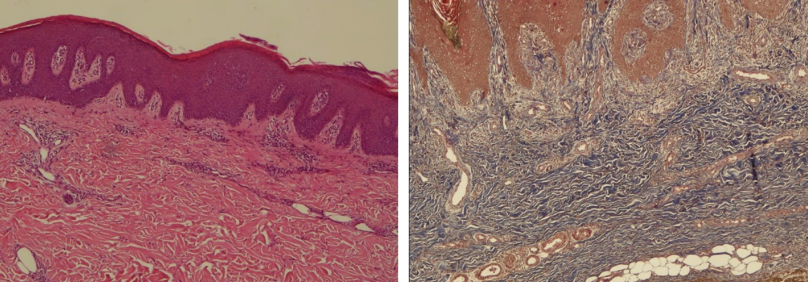

Bệnh nhân được tiến hành sinh thiết da hai lần. Kết quả giải phẫu bệnh lần 1 (01/2026) cho thấy hình ảnh tăng sản thượng bì dạng vảy nến, kèm theo nhiều tế bào dị sừng. Kết quả lần 2 (03/2026) ghi nhận thượng bì tăng sản dạng vảy nến, dày sừng và á sừng, kèm theo phản ứng viêm dạng lichen và tăng sinh collagen. Nhiều tế bào dị sừng (dyskeratotic cells) xuất hiện rải rác trong lớp gai. Nhuộm Masson ba màu xác nhận tình trạng tăng sinh collagen lan tỏa tại trung bì.

Về mặt mô bệnh học, dấu hiệu then chốt để xác định TAMA là hiện tượng interface dermatitis kèm theo các tế bào dị sừng (dyskeratotic cells). Cơ chế này đã được làm rõ trong các nghiên cứu của Miyagaki et al. (2013), theo đó các lympho bào T CD8+ xâm thâm nhiễm lớp đáy thượng bì và kích hoạt quá trình chết tế bào theo chương trình (apoptosis) của các tế bào gai. Đây là đặc điểm tương đồng với bệnh Ghép chống chủ (GvHD), gợi ý rằng khối u tuyến ức đã tạo ra một môi trường nơi các tế bào T không còn khả năng phân biệt giữa kháng nguyên tự thân và kháng nguyên ngoại lai.